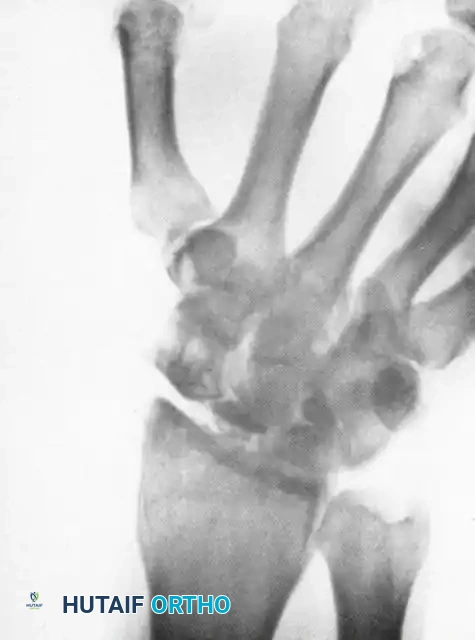

Image

Above: Long-standing scaphoid nonunion demonstrating advanced arthrosis, osteonecrosis, collapse of the proximal pole, and the pathological settling of the capitate into the proximal carpal row.